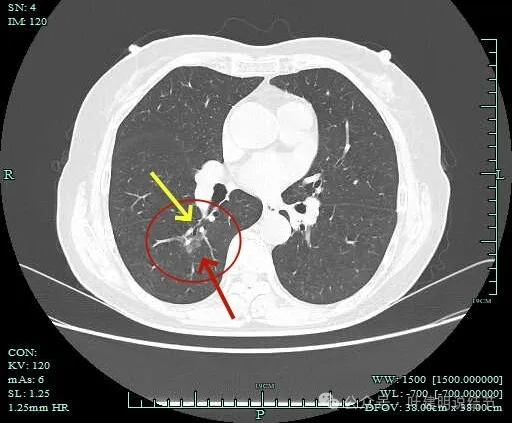

病灶出现,淡磨玻璃密度,但轮廓较清,且表面不平。

病灶内部有走行的支气管,但显得有些僵硬;病灶表面有浅分叶。

灶内血管走行,轮廓与边界清楚。

边缘有毛刺征!

沿支气管走行方向延伸,磨玻璃密度,且支气管内壁显得毛糙。

毛刺明显,轮廓清楚,灶内支气管扩张通气。

毛刺明显,灶内有实性成分出现。

毛刺征明显!!灶内密度杂乱。

实性成分较多,边缘毛刺。

毛刺征明显,而且是短毛刺且锐利。

毛刺。

边缘区也不光滑,显毛糙。

靶重建显示混合密度,边缘毛糙,内部杂乱,灶内支气管通气且僵硬。

病灶影响到斜裂肺门部,边缘毛刺明显。灶内支气管僵硬。

密度杂乱,毛刺明显,支气管僵硬。

杂乱密度,整体轮廓较清,边缘毛糙。

斜裂根部有增厚并与病灶连着。考虑是肿瘤已经侵及叶间裂。

病灶边缘毛刺明显。

肺磨玻璃结节我们常说瘤肺边界清楚加上随访持续存在,基本上是肺癌性质的。但像今天这种混合磨玻璃密度的病灶,你看它瘤肺边界却是不清楚的,只是整体轮廓相对较清。但它的瘤肺边界是布满细毛刺的,而且是短毛刺且锐利,在影像上就像刺入周围正常肺组织中。这种影像表现的我将它称为“浸润性生长的影像表现”,说明病灶是浸润性病灶,而非原位癌或良性。这样的病灶不宜过度随访,需要及时干预更为稳当。